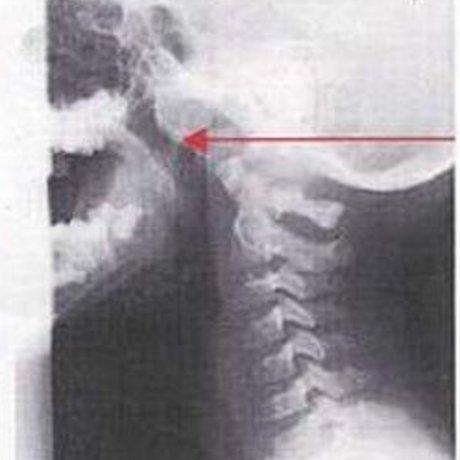

До лечения: у четырёхлетнего пациента аденоиды III степени.

После лечения аденоиды полностью рассосались и носовое дыхание восстановлено.

До лечения: на рентгене мы видим гигантские аденоиды, которые спускаются из носа в глотку. Пятилетний пациент не мог дышать носом.

После лечения носовое дыхание восстановлено и аденоиды рассосались.

Рентгенограммы, подтверждающие эффективность лечения, имеются только в нашей клинике и являются собсвтенностью доктора Сичинава.